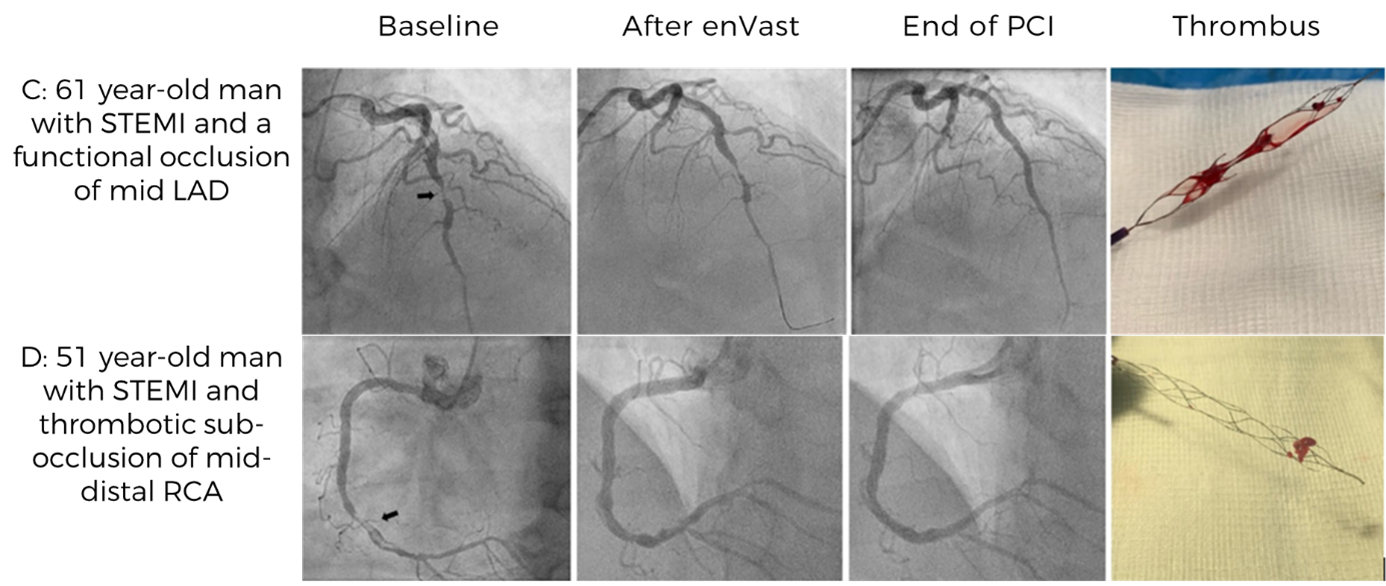

In a first-in-human case series of 61 STEMI patients with LTB, a thrombectomy technique with an enVast stent retriever and continuous aspiration was developed for coronary care.

The technique was safe and warranted high rates of successful flow restoration in culprit vessels​

Dr. Marco Vaglimigli, Deputy Chief of Cardiology at Cardiocentro Ticino Istituto, Switzerland, uses enVast in STEMI patients

enVast devices with freshly removed LTB clots inside